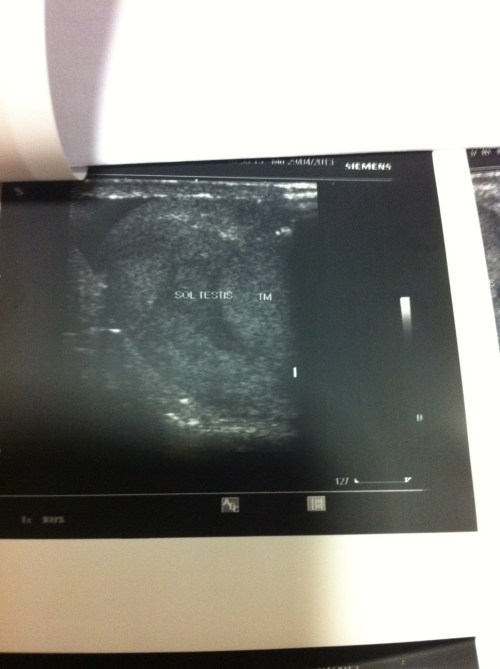

Küçük ve karanlık bir odaya girdiğimde doktor bey de içerideydi. Ultrason makinasının ekranı karanlıktı. Doktor, şikayetimin ne olduğunu, ne zaman başladığı, ağrı olup olmadığını sordu. Radyolog, kısa boyluydu, hafifçe göbeği vardı, karanlık da çalışmaktan derisinin rengi soluk gözüküyordu. Dr. Ufuk bu yüzden “bizim batman sana bir baksın, anlarız ne olduğunu” diye söylemişti ve ben bu espriyi yeni anlamıştım: yarasalar gibi karanlıkta çalışıyordu radyologlar. Saç jölesi gibi bir şeyi cildime sürdü doktor, soğuğundan irkildim aniden ve ekranda bazı beyazlıklar belirdi. Bir ekrana, bir doktora bakıyordum, sanki televizyon da yayın bitmiş, İstiklal Marşı okunmuş ve karlı ekran başlamıştı. Hiçbirşey anlaşılmıyordu.

-“Sol testisde bir kitle var, şimdi dopplerle bakacağım. Evet, kitle oldukça kanlanıyor.”

SOL TESTİS’de tm. mevcuttur. Kitle testisin asgari 2/3’ünü kaplamaktadır. Kitle multilokal- multilobüle (bulky) görünümdedir. Az miktarda kalan normal doku içinde mikrokalsifikasyona rastlandı. Kitleler çoğunlukla hipoekoiktir. Bir kısmında rim şeklinde hiperekojen kapsüler eko (kalsifikasyon?) izlendi.

RENKLİ DOPPLER’de sol testiküler solid kitle ileri derecede hiper vaskülerdir (malignite kuvvetle muhtemeldir).

SOL TESTİS TM.

SOL TESTİKÜLER MİKROLİTHİAZİS.